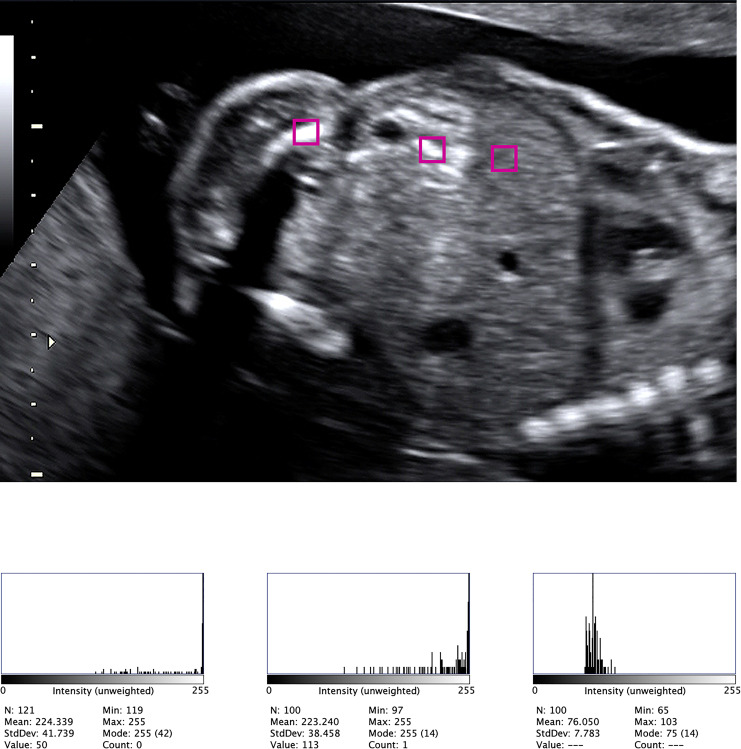

Methods: This is a single-center retrospective study including all fetuses with a diagnosis of echogenic bowel (FEB) in the mid-second trimester between 2015 and 2021. Ultrasound images were analyzed using ImageJ software. The mean of the grayscale histograms of the bowel, liver, and iliac/femur bone was obtained for each patient, and the ratio between these structures was used to overcome gain variations. We compared these values with those of a matched control group of singleton uncomplicated pregnancies and with a group of patients referred for FEB, where the FEB was not confirmed by the expert operator (FEB false-positive).

Results: There was a statistically significant difference between bowel/liver and bowel/bone histogram ratios between the FEB group and the control groups (p < 0.05). Mean ratio cutoffs were provided for the diagnosis of FEB. Among the patients with confirmed FEB, both ratios were not able to discriminate the cases with adverse outcomes. In contrast, the presence of dilated bowel or other markers was associated with an adverse outcome.